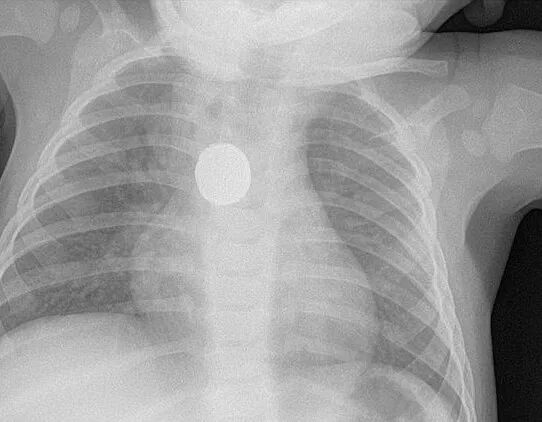

随后到了医院后,Brittney立刻就被送进了急救室。但突然的大出血,让医生们也不清楚小Brittney究竟伤在了哪里,只好给Brittney安排了X光检查。

结果,这一检查不要紧,医生立刻就发现了Brittney身体的异样。在X光片里,清晰的照出,Brittney两肺之间卡着一个圆形异物!

而经过对比、排查后,最终判定,这个异物正是家家户户都会有的纽扣电池!